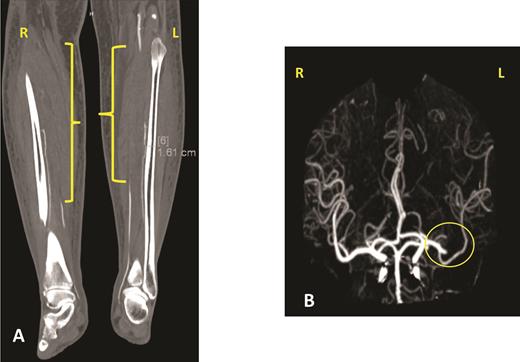

The patient’s hospital course in December 2019 was complicated by acute on chronic diastolic heart failure with preserved ejection fraction, new splenic infarct, acute lower extremity limb ischemia requiring revascularization, acute ischemic stroke involving the proximal inferior left M2 branch requiring mechanical thrombectomy, and a new lower extremity deep venous thrombus, all within a two-week period (Figure 3). After recovering from this hospitalization, the patient was started on treatment for AL amyloidosis with cyclophosphamide, bortezomib, and dexamethasone (CyBorD) in January 2020. Unfortunately, after one cycle of CyBorD, the patient developed gastrointestinal hemorrhage and recurrent stroke. A new left atrial thrombus was seen on TTE, despite ongoing anticoagulation with apixaban (Figure 4). The patient and family opted for comfort care at this time and the patient died shortly thereafter.

Panel A shows one of the views of a computed tomography angiogram of the lower extremities. The yellow brackets indicate areas of stenosis or occlusion in both lower extremities. The patient was found to have an occluded right popliteal artery, right anterior and posterior tibial artery, right tibioperoneal trunk, and right and left peroneal artery. She had different degrees of occlusion in those vessels. Panel B shows a cerebral angiogram, with the yellow circle indicating the occlusion of the proximal inferior left M2 branch.